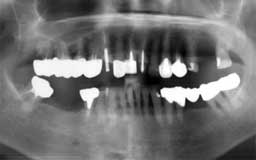

Eさん 初診時 53歳 女性

残存歯数26本とはいえ、10代のころみたいな万全な状態の歯は1本もなく、クラウンの中は 虫歯、歯周疾患も末期の状態です。徹底的な治療とメインテナンスが必要と思われます

Eさん 12年後 65歳

治療やメインテナンスに対する理解が得られず、主訴のみの治療で来院が途絶えてしまいまし た。その後他院を転々と受診したそうですが、約10年間に予想通り大半の歯を喪失

Eさん 17年後 70歳

再来院後は毎月のメインテナンスを継続され、今のところ何とか残存歯がそのまま機能してい ます